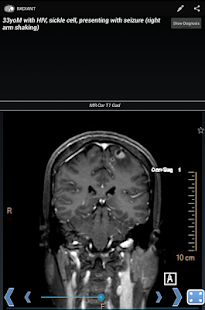

RADIANT: Share Radiology Cases Screen Preview

RADIANT is a platform to create, manage, and share image-based educational materials, primarily intended for users in the medical field. It is ideal for sharing interesting cases among diagnostic radiology residents, fellows, medical students, and faculty. It is NOT meant to be used for diagnosis.

Content is organized around a single image as the fundamental component. Multiple related images comprise a series, which allows for scrolling through the image stack. These image series form the building blocks for Cases (related series demonstrating the imaging findings for a specific diagnosis in one particular patient), Teaching Files (topics organized in chapters and sub-chapters like a text book), and Tests (linked questions with associated image series). Cases can be grouped together in to Case Packs, which take only seconds to create, and are perfect for last minute unknown case presentations and focused studying.

With RADIANT, you can create cases showing x-rays, ultrasound, CT, MRI, or any other imaging modality. It is a great way to learn chest x-rays, normal anatomy, and common disease processes, using real, high-quality diagnostic medical images.